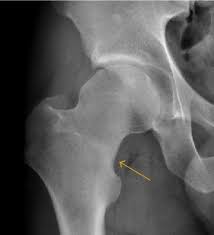

피로 골절이 자주 생기는 부위

피로 골절은 반복적으로 체중이 실리는 부위에서 흔히 발생합니다. 특히 아래 부위는 비교적 자주 언급됩니다.

• 발등과 발바닥 앞쪽

• 정강이 뼈 주변

• 발목과 뒤꿈치 근처

• 장시간 서 있거나 걷는 경우 무릎 아래 부위

러닝이나 등산을 갑자기 시작했거나, 평소보다 활동량이 급격히 늘어난 경우, 또는 딱딱한 바닥에서 오래 서 있는 생활이 이어졌다면 위험이 커질 수 있습니다.